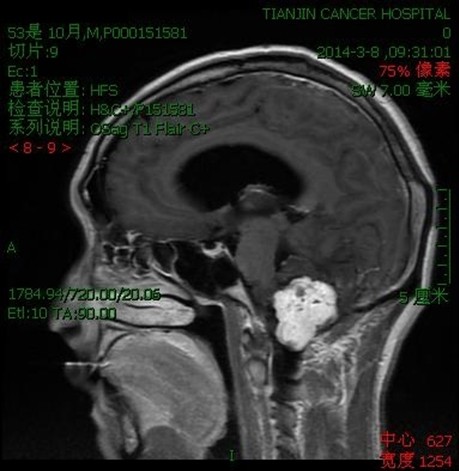

病例二:王**,男性,53岁。因做小脑肿瘤术后9年,头痛头晕,伴颈部疼痛、走路不稳半年入院。入院诊断:延颈交界血管网织细胞瘤。术式:后正中入路延颈交界区血管网织细胞瘤切除术。术后病理:血管网织细胞瘤。术后头痛头晕,颈部疼痛消失,走路平稳。

术前